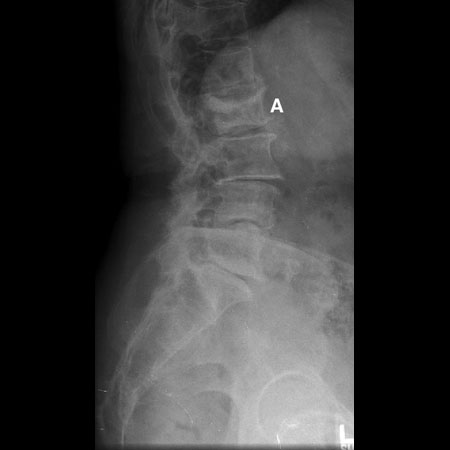

კომპრესიული მოტეხილობის რენტგენი: ლატერალური პროექციის რენტგენი L2 კომპრესიული მოტეხილობის დროს (A). შეინიშნება მალის სხეულის სოლისებრი დეფორმაცია

ექიმ Dr K. Singh საკუთრება; გამოყენებულია ნებართვით